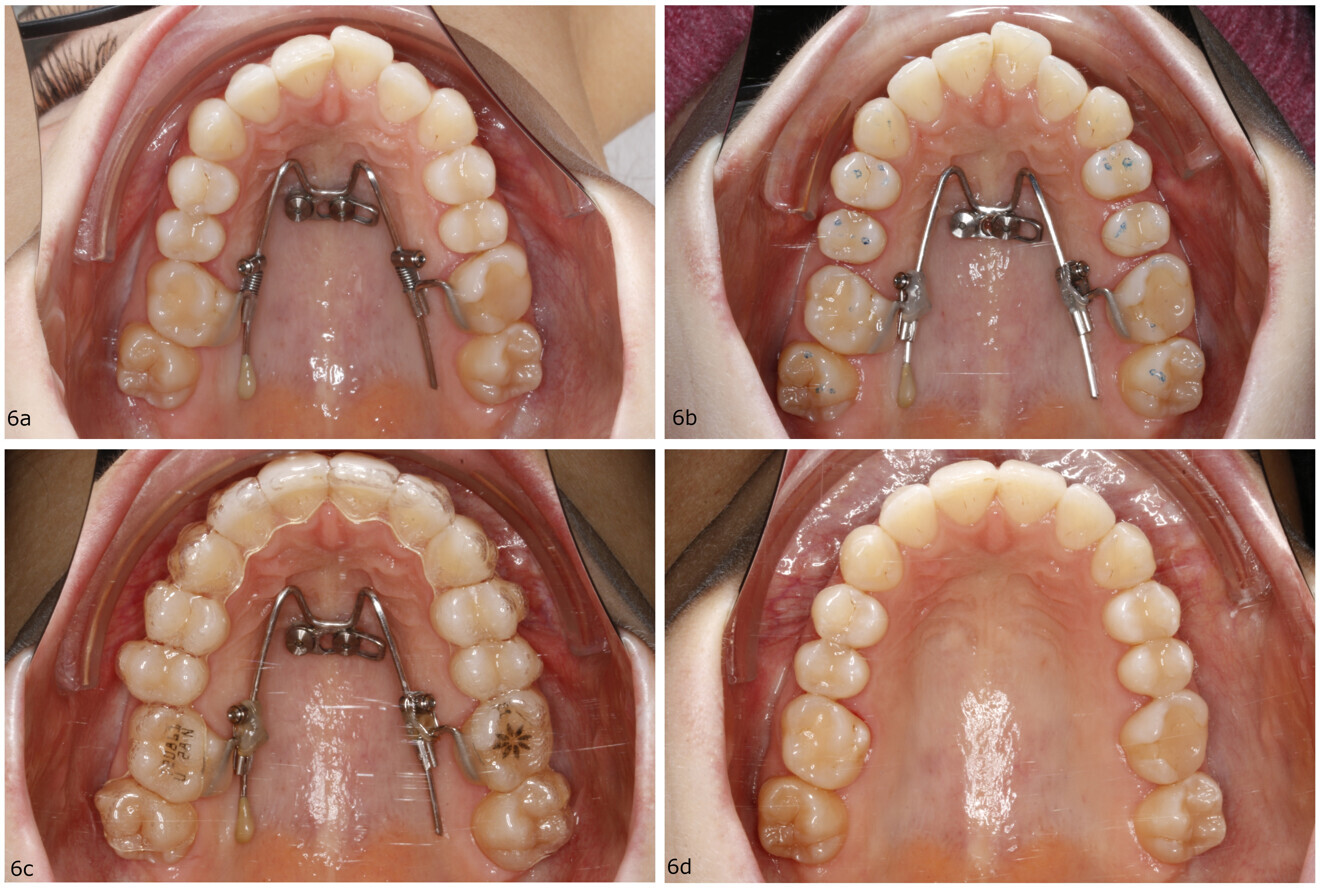

Figs. 8a–d: Treatment progress of a 13-year-old female patient with a severe maxillary transversal deficiency. (a) Insertion of two mini-implants in the anterior palate and the BMX expander. (b) Expanded maxilla after four weeks of activation. (c) Subsequent aligner finishing. (d) Result.

Clinical case (BMX expander)

A 13-year-old female patient presented with a severe maxillary transversal deficiency. The patient and her parents requested treatment with aligners and made an informed decision to proceed with treatment using a mini-implant-borne expander for the maxilla and aligners for levelling of the teeth afterwards.

The treatment started with insertion of two mini-implants (2 × 9 mm) in the anterior palate under local anaesthesia (Fig. 8a). A prefabricated BMX expander (8 mm; PSM) was first adapted by pre turning the expansion screw directly chairside and fixed with two fixation screws. Expansion activation was initiated by performing one activation per day for a total of about 0.2 mm expansion per day. After four weeks of activation, the maxilla had been expanded by approximately 5.5 mm (Fig. 8b). Subsequently, scans were taken for the aligner finishing (ClearCorrect). The BMX expander was kept in place for skeletal retention (Fig. 8c). The aligner treatment was finished after ten months (Fig. 8d). The whole treatment duration was 12 months (one month of expansion, one month for aligner manufacture and ten months of aligner finishing).